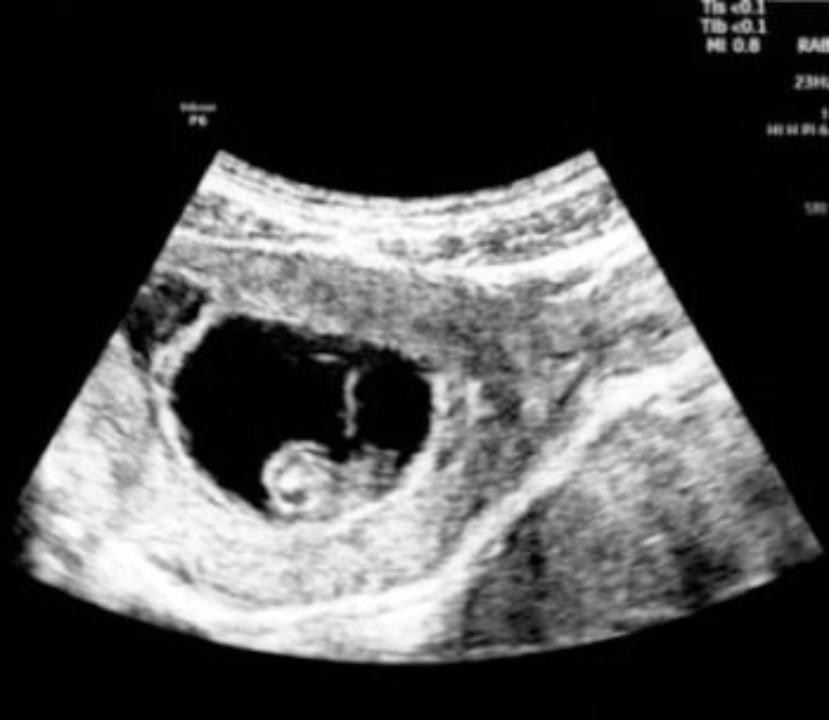

HOW EARLY ULTRASOUNDS WORK AND WHAT THEY LOOK LIKE.

A fetal ultrasound, also called a sonogram, produces images of your baby in the womb by using high-frequency sound waves

Early ultrasounds are done in the first 14 weeks of pregnancy and show images of the baby’s early development stages. (3) Routine ultrasound images are typically black and white. They are usually somewhat fuzzy but are detailed enough to show us what we need to know about fetal growth. For this reason, it may not be easy for you to identify exactly what you are seeing on the screen. We’ll help you understand what we’re seeing and what it means. We will also give you the option of keeping a few printed images from the scan.

There are a few things you will notice when you look at the ultrasound screen. You will see a white image of your baby and umbilical cord, against a dark background. Your doctor will learn a lot of important information about your developing baby by observing these images.